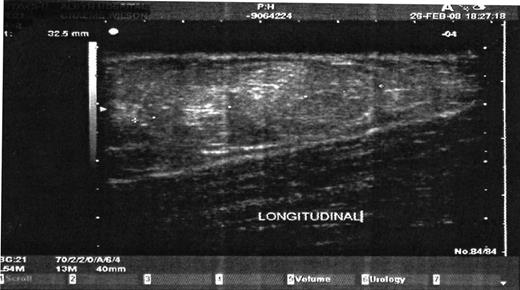

On examination, a 10 × 5 cm lesion was identified in the medial aspect of his left upper thigh. This was discrete from genitalia and was associated with a nipple areolar complex (Fig. 1 and 2). A smooth, well-defined edge to the mass was noted. There were no firm masses within the lesion and no nipple discharge could be elicited. Abdominal, testicular and neurological examination showed no abnormal findings. On assessment of his biochemical endocrinology profile, all parameters were within normal ranges. An ultrasound examination of the left thigh was consistent with mixed density breast tissue but no evidence of malignancy.